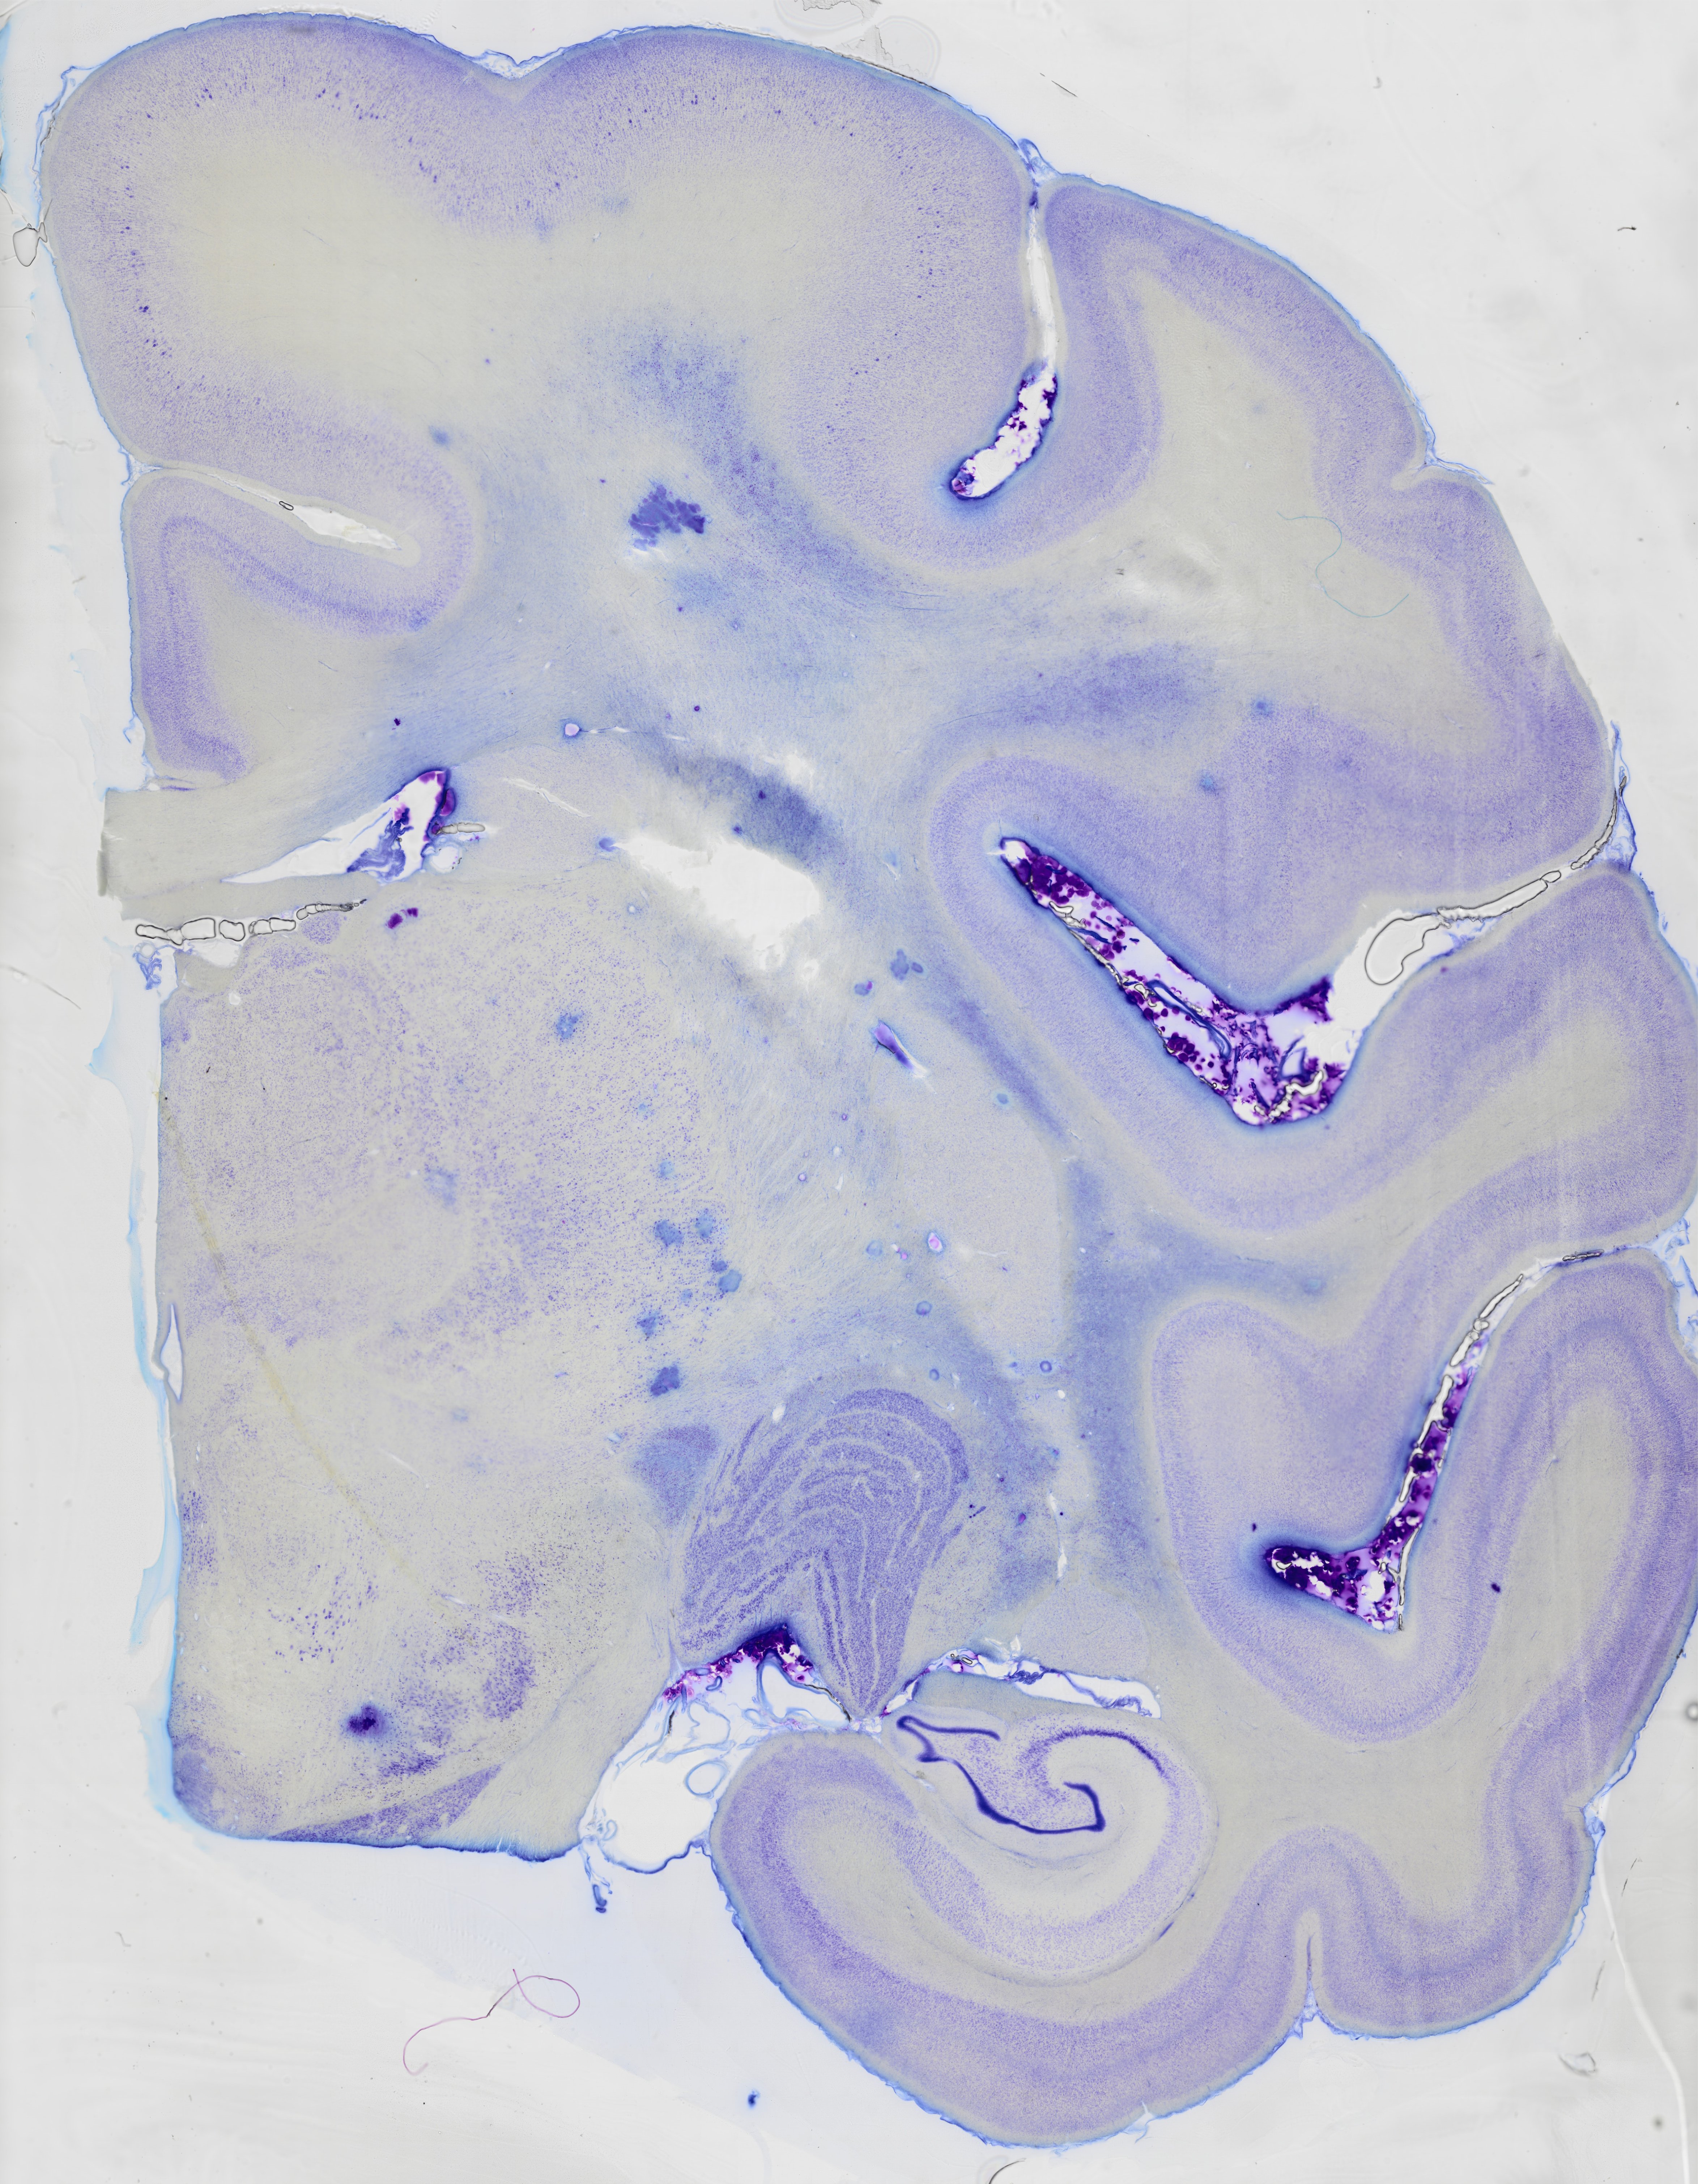

The brain of the macaque Macaca nemastrina

Move your mouse over the brainslice to observe the details

Macaque hippocampus

zoom box